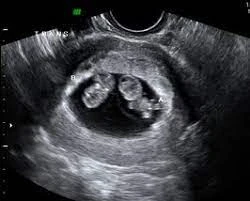

إذا كنت تريدين حقًا معرفة جنس طفلك لتقرر شيئًا مثل اختيار لون للغرفة أو شراء ملابس لطفلك مبكرًا، فالطريقة الوحيدة لتكوني دقيقًة هي الذهاب إلى الموجات فوق الصوتية.

أفضل وسيلة هي الموجات فوق الصوتية (السونار)، وعادة يمكن تحديد الجنس بدقة من الأسبوع 14 – 20 من الحمل.